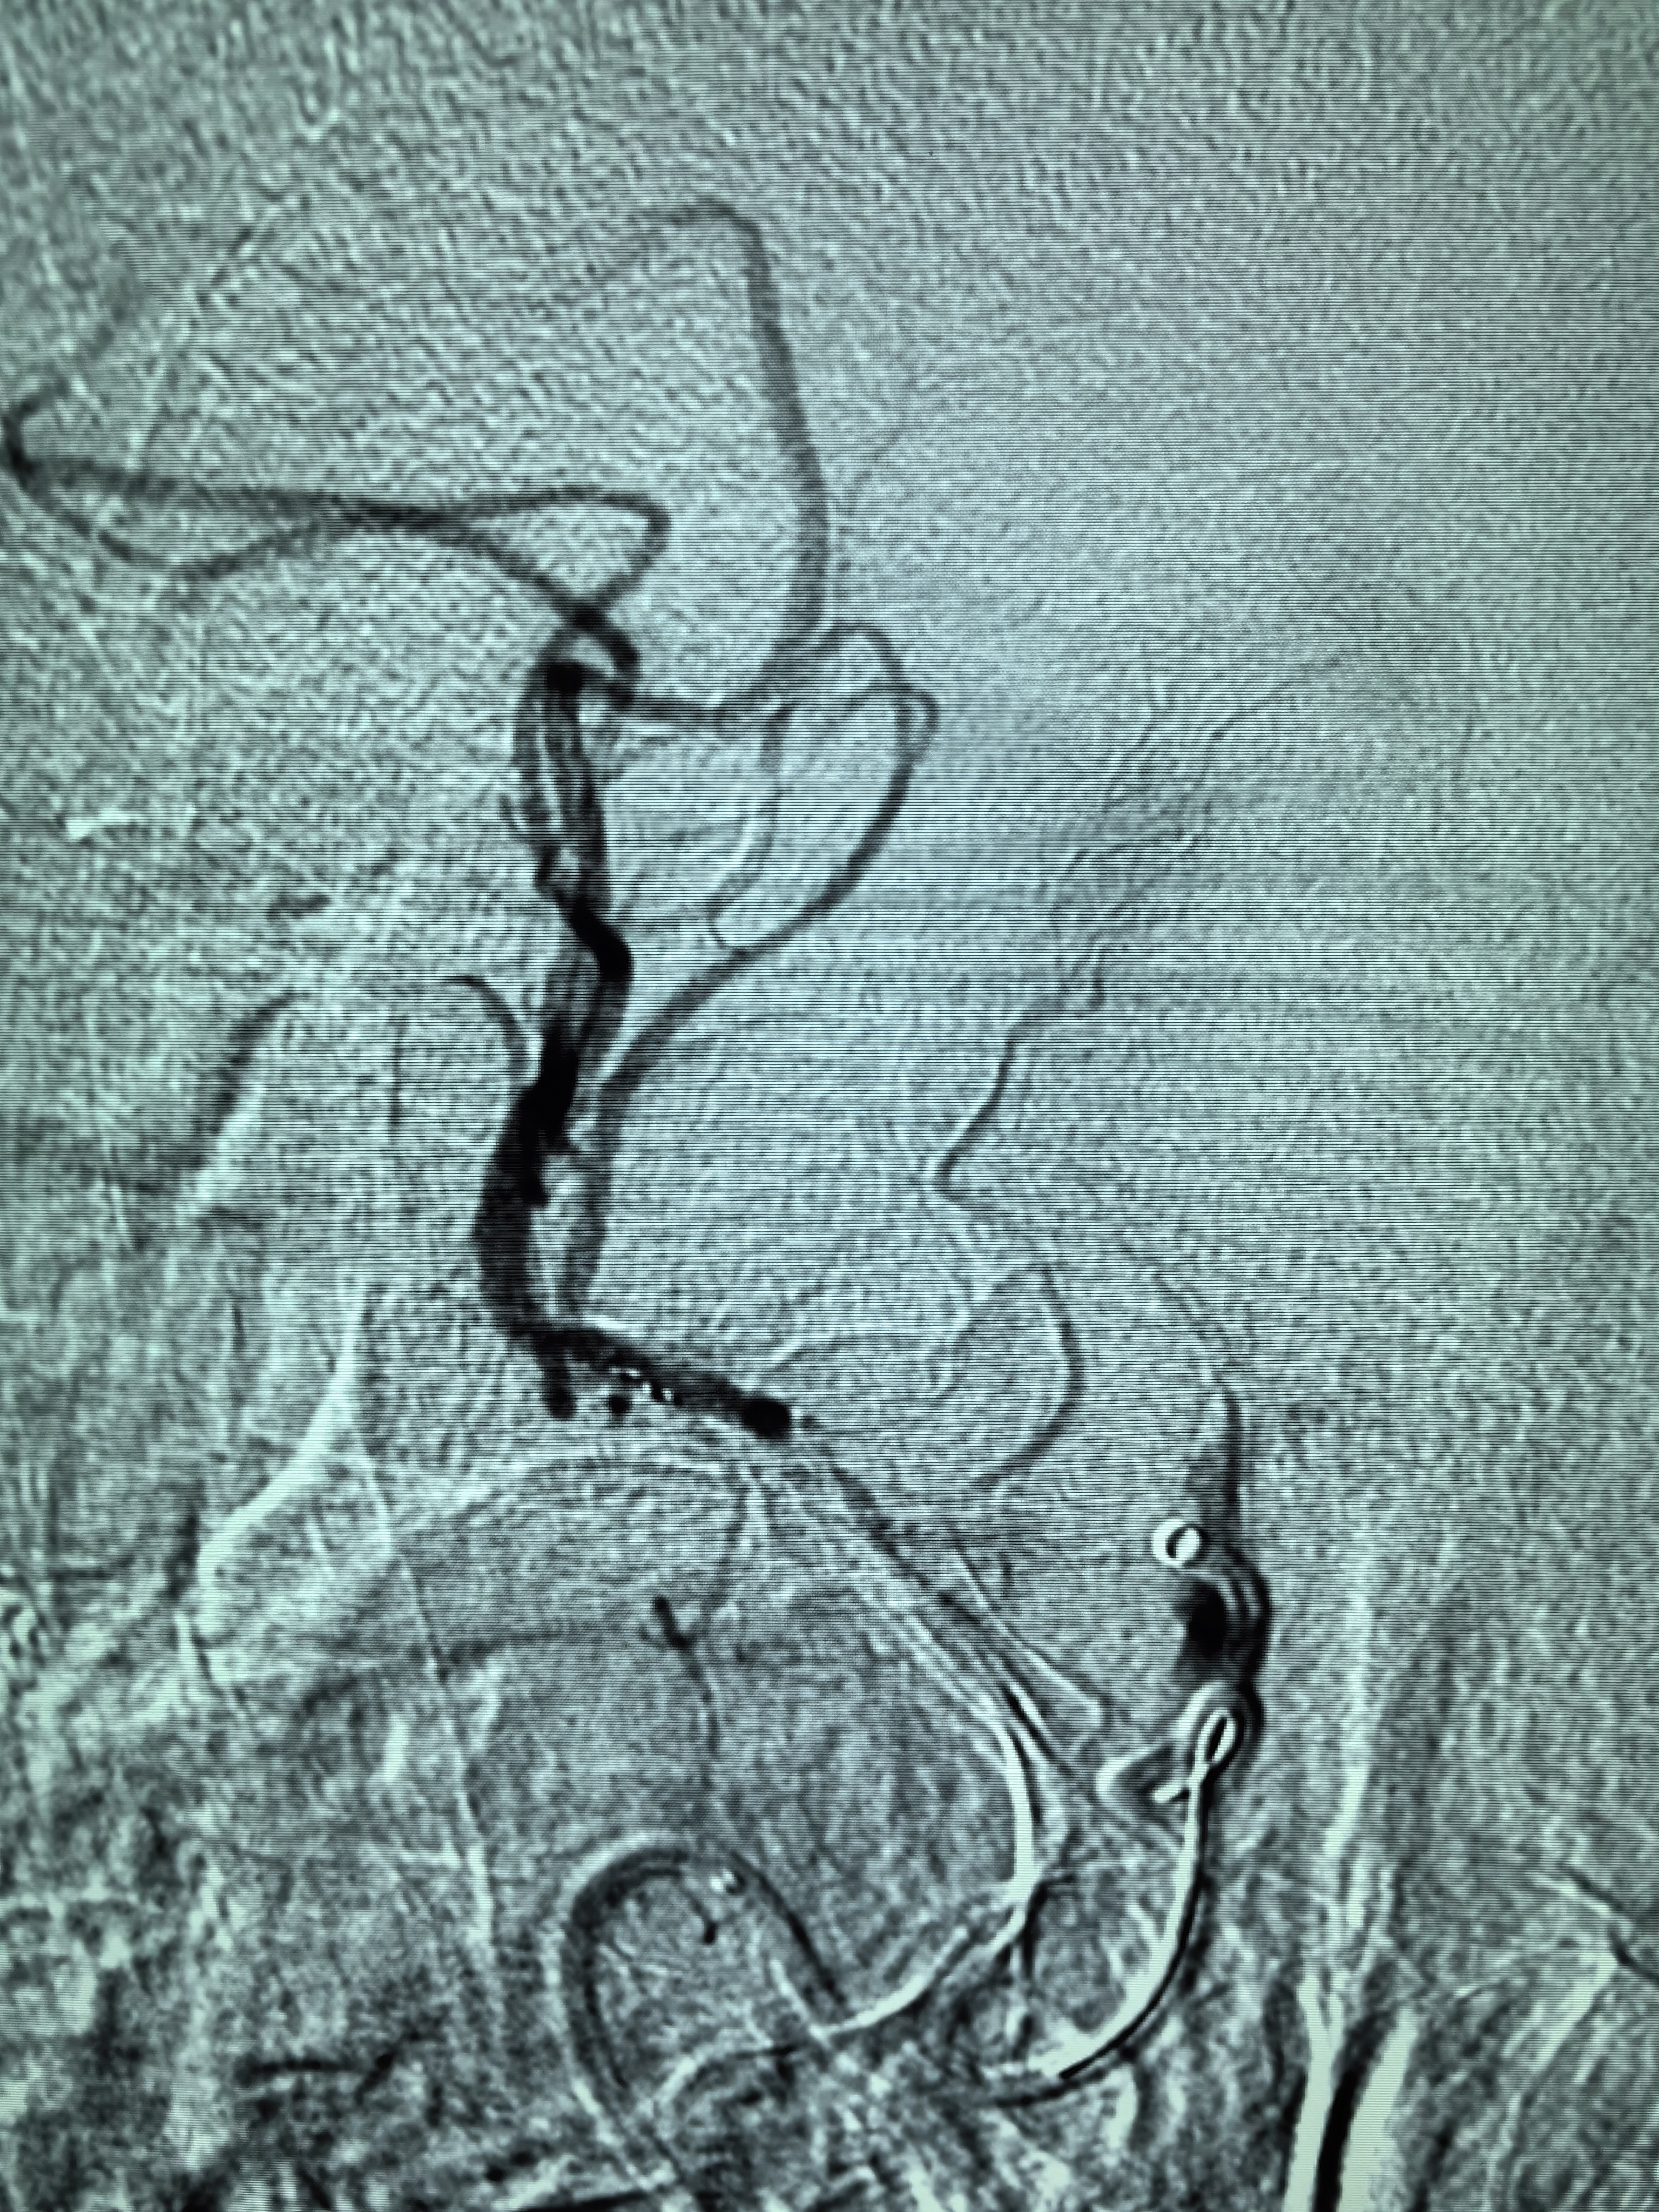

患者术前明确右侧颈内动脉系统栓塞,遂快速建立8F导引导管+CAT6中间导管取栓路径,微导丝携微导管顺利通过病变。

3、SWIM技术有效开通颅内大负荷血栓后应积极预防再灌注损伤,积极控制脑水肿。